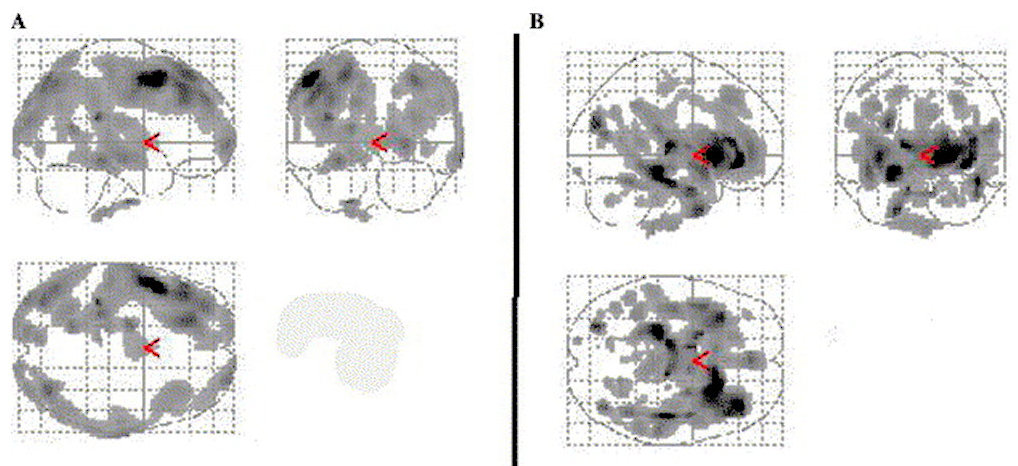

- Relative to control subjects, both peripheral and central pain patients showed significant opioid receptor binding decreases in a number of regions. In the central post-stroke pain (CPSP) group binding decrease was clearly asymmetrical (Fig. 2A). And predominated in the hemisphere contralateral to pain in the lateral prefrontal cortex, the insula, medial thalamus, posterior temporal cortex and posterior midbrain.

The only region with strictly bilateral BP decrease in CPSP patients was the anterior cingulate, in particular its perigenual region. - In contrast, the peripheral neuropathic pain (NP) group showed bilateral and symmetrical decrease in binding. Which concerned the insula, thalamus (mainly medial), anterior cingulate, posterior temporal and orbitofrontal cortices, posterior midbrain and striatum (Fig. 2B). No region with binding increase was noted in patients relative to controls. [1]

Statistical parametric significance map

- This map showing sagittal, coronal and axial projections of structures with reduced opioid binding in patients relative to matched controls: Reduction in the CPSP group was asymmetrical and lateralised to the hemisphere contralateral to pain (A), while in the peripheral NP group (B) binding decrease was symmetrical.